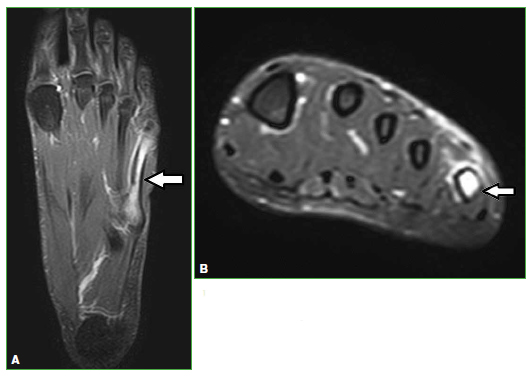

Figura 7.

Lesión del complejo extensor de la mano. Resonancia magnética, secuencias STIR. Cortes sagital (A) y axial (B). Las flechas señalan el cambio de señal adyacente al tendón común de los dedos.